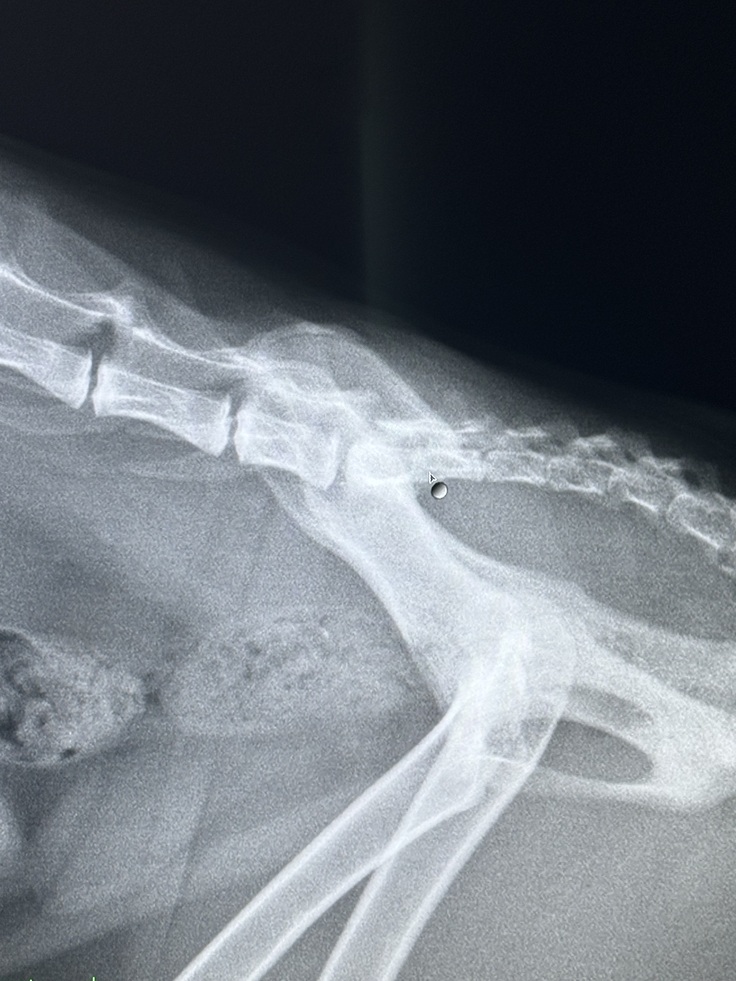

病院に行くと骨盤骨折…

ただ、レントゲンではかなり難しい手術になりそうとのことでした…